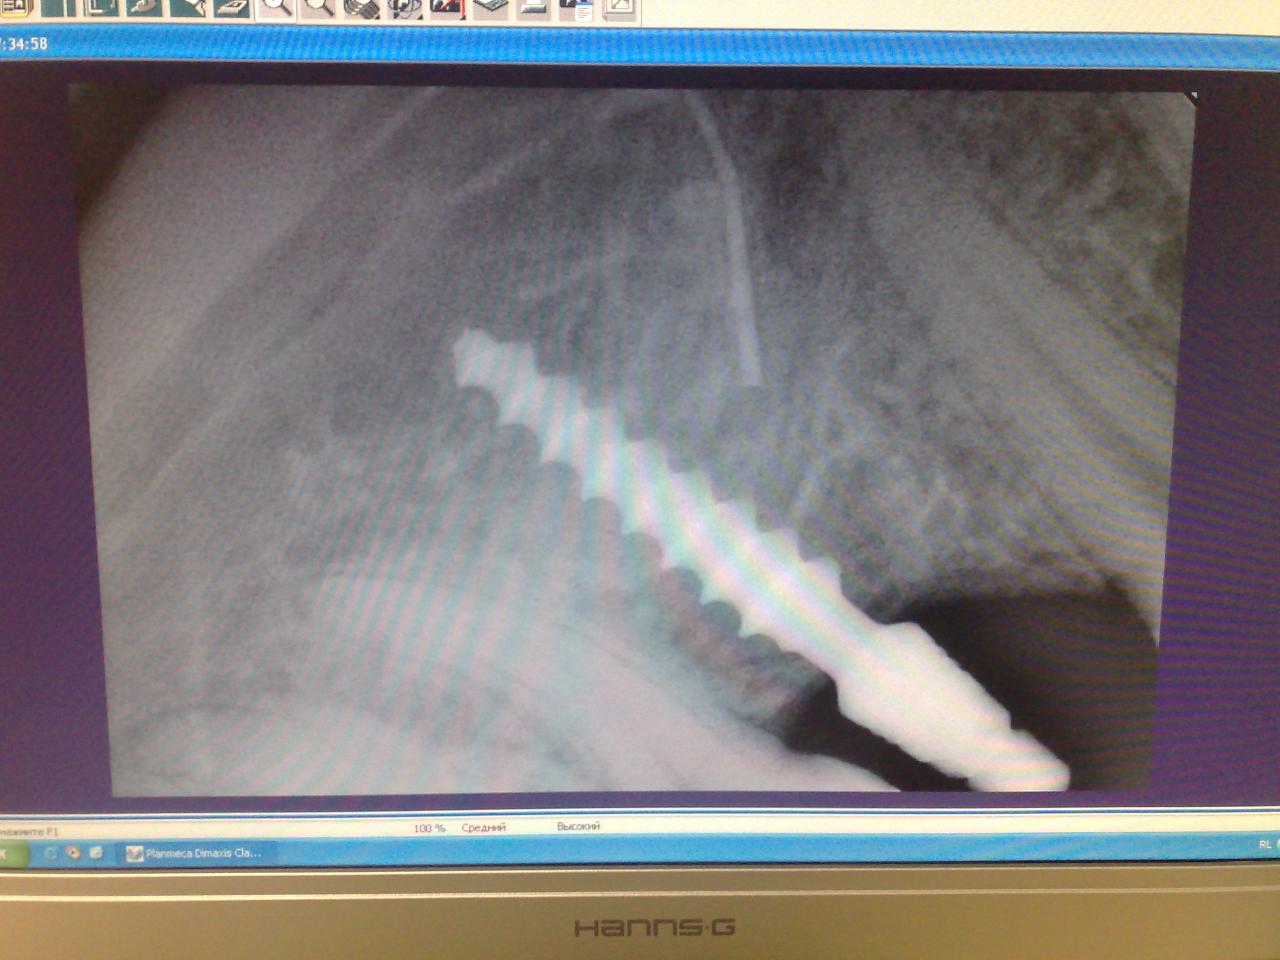

Сделали, фото снимка:

Вложение 4882047

В понедельник еду на прием,т.к. мне поставили просто "саморез" без временной коронки, а он царапает язык.

А еще до 21 года имплантаты лучше не ставить.

И временную коронку, на одиночно стоящий одноэтапный имплантат я бы не рискнул...